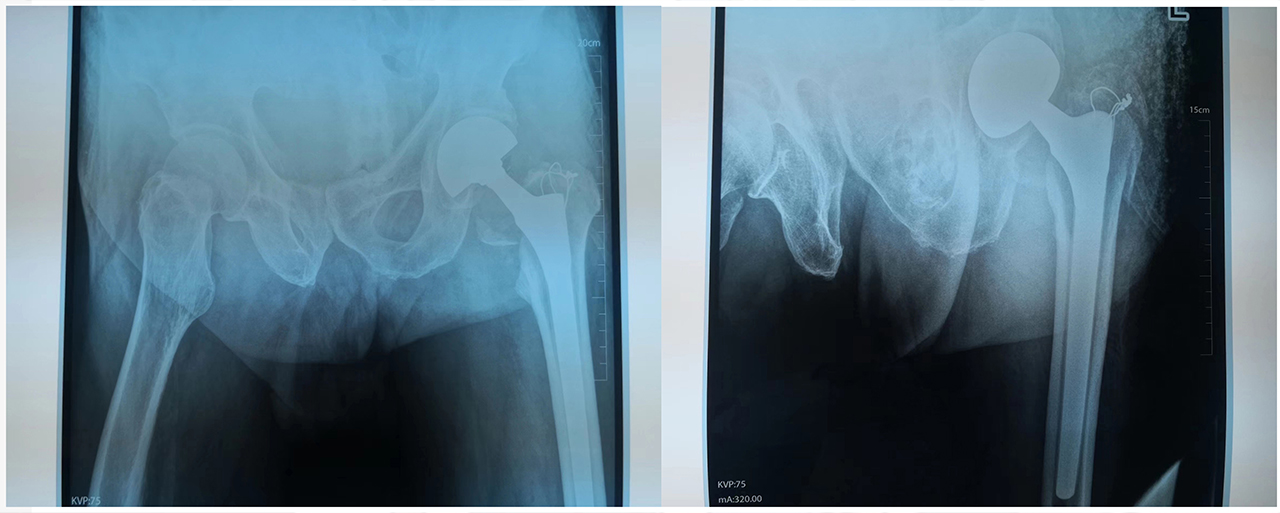

图说:患者术中DR片

股骨头置换术后的护理同样非常的重要,护士对大爷及家属进行了健康宣教,帮助患者做了如何坐立、上下床的练习,最终在我们医护人员的共同努力下,患者下地走路了,露出了满意的笑容。